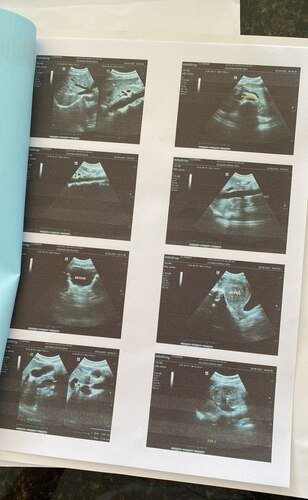

01 - Cirurgia um mioma que está entre o útero e o intestino e isso me impede de defecar, causando desconforto e ressecamento.

O mioma está crescendo muito rápido porque o meu sangramento é muito intenso e o sangue faz com que ele cresça e desenvolva com muita rapidez, pois já está quase uma gestação de cinco meses empurrando o intestino e o útero que aumentou de tamanho.

E foi quando descobri a pedra na vesícula fazendo os exames sendo assim mais uma cirurgia a ser feita.

02 - Cirurgia de pedra na vesícula, que ao realizar o exame de ultrassom apresentou.